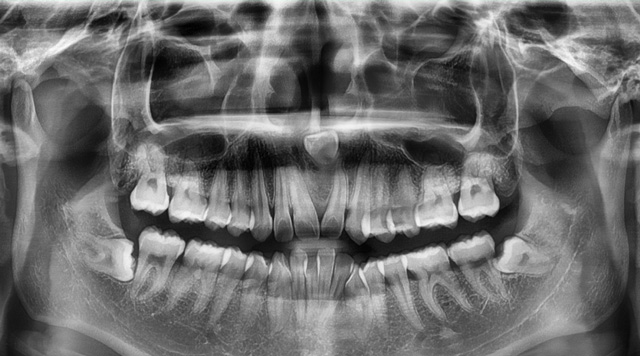

医生怎么能知道这颗牙的情况呢?只用肉眼看是不够的,我们要通过口腔全景片、CBCT这些影像学检查资料来了解牙齿的解剖位置,了解牙根的数量和形态,以及有无根尖囊肿和炎症。

以上这些情况都需要在术前充分了解,这就是我们拔牙前要拍片检查的原因。